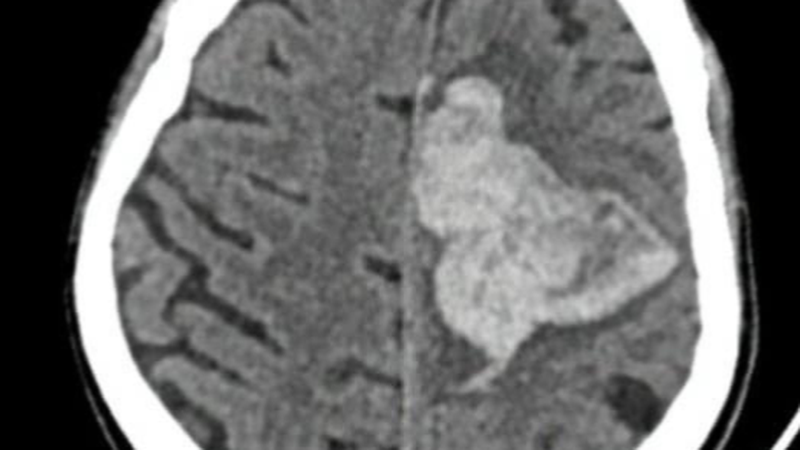

Hình ảnh chụp cắt lớp vi tính sọ não người bệnh. Ảnh: BVCC

Khi thăm khám, bệnh nhân có các biểu hiện lơ mơ, nôn ói, liệt nửa người, babinski bên phải; chụp cắt lớp vi tính sọ não (CT scan) và chụp mạch máu não (CTA) cho thấy có tình trạng xuất huyết nhu mô não thùy trán trái lượng trung bình, tràn não thất do vỡ dị dạng mạch máu não (AVM). Bệnh nhân được nhanh chóng chuyển lên phòng can thiệp mạch máu não với phương pháp nút keo gây tắc mạch máu, sau can thiệp bệnh nhân được theo dõi tiếp tại Khoa hồi sức COVID.